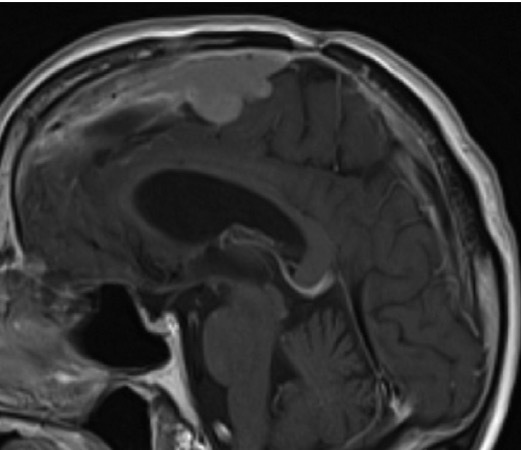

大多数前颅窝和中颅窝脑膜瘤可以从根本上切除。然而,即使随着手术器械、神经影像学和神经监测的发展,与前颅窝或中颅窝脑膜瘤相比,后颅窝脑膜瘤...

脑膜瘤治疗的预后情况、并发症的发生率、恢复时间与肿瘤位置、生长特点、术者的技术经验等息息相关,对于解剖位置比较复杂的脑膜瘤,例如枕骨大孔...

鞍结节脑膜瘤95%以上为良性肿瘤。鞍结节脑膜瘤生长在前颅底与中颅底交界处的鞍结节,起源于硬脑膜,向上生长。鞍结节脑膜瘤一般压迫患者视神经,导...